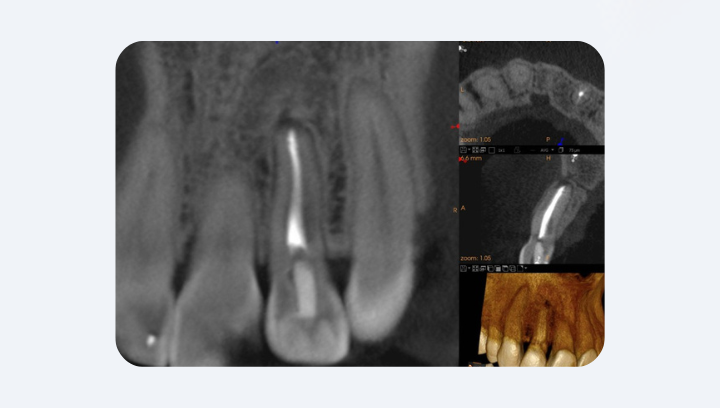

Лечение каналов

У многих зубов есть варианты анатомии: два канала в одном корне, слияния или изгибы, которые просто не видны в 2D. CBCT показывает реальную трёхмерную структуру. Именно благодаря этому современная эндодонтия стала точнее и менее травматичной. А ещё CBCT позволяет выявить скрытые перфорации или остаточные очаги поражения, которые не видны на рентгене. Это означает: если болит зуб, который «лечили полгода назад», именно КТ покажет причину, а не догадку.

▪️ Зачем КТ перед лечением каналов?

Потому что рентген не показывает всю анатомию корней. На КТ видны все каналы, в том числе дополнительные или слившиеся, которые часто остаются незамеченными. Можно определить, есть ли воспаление за верхушкой, где именно оно расположено, есть ли перфорация или трещина. Такая точность позволяет провести лечение один раз — качественно и без повторных болей из-за «невидимых» каналов.

Да. Трещины часто не видны ни на рентгене, ни под микроскопом, если они проходят внутри корня. КТ показывает такие дефекты благодаря высокой разрешающей способности (0,04 мм). Это помогает решить — можно ли сохранить зуб или лучше заменить его имплантатом. Поэтому в сложных, непонятных случаях КТ — единственный способ поставить точный диагноз.